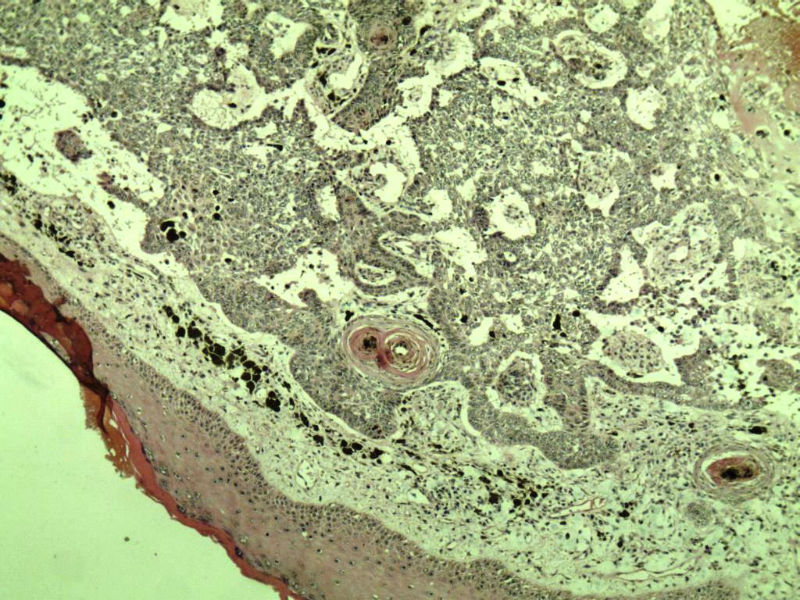

这是另外一个  75岁 男性 脸上有一直径0.8cm新生物 是鳞癌吗? 感觉细胞异型性不够大.

第二例:基底细胞癌

第二例,两种成分,1、毛发上皮瘤;2、皮内痣。

第一例考虑毛母细胞瘤,第二例考虑基底细胞癌。

第一例:毛母细胞瘤;第二例:基底细胞癌

第一例,毛发上皮瘤;第二例,基底细胞癌。

1.BCC.  2.BCC.

二基底细胞癌。

两例均为BCC